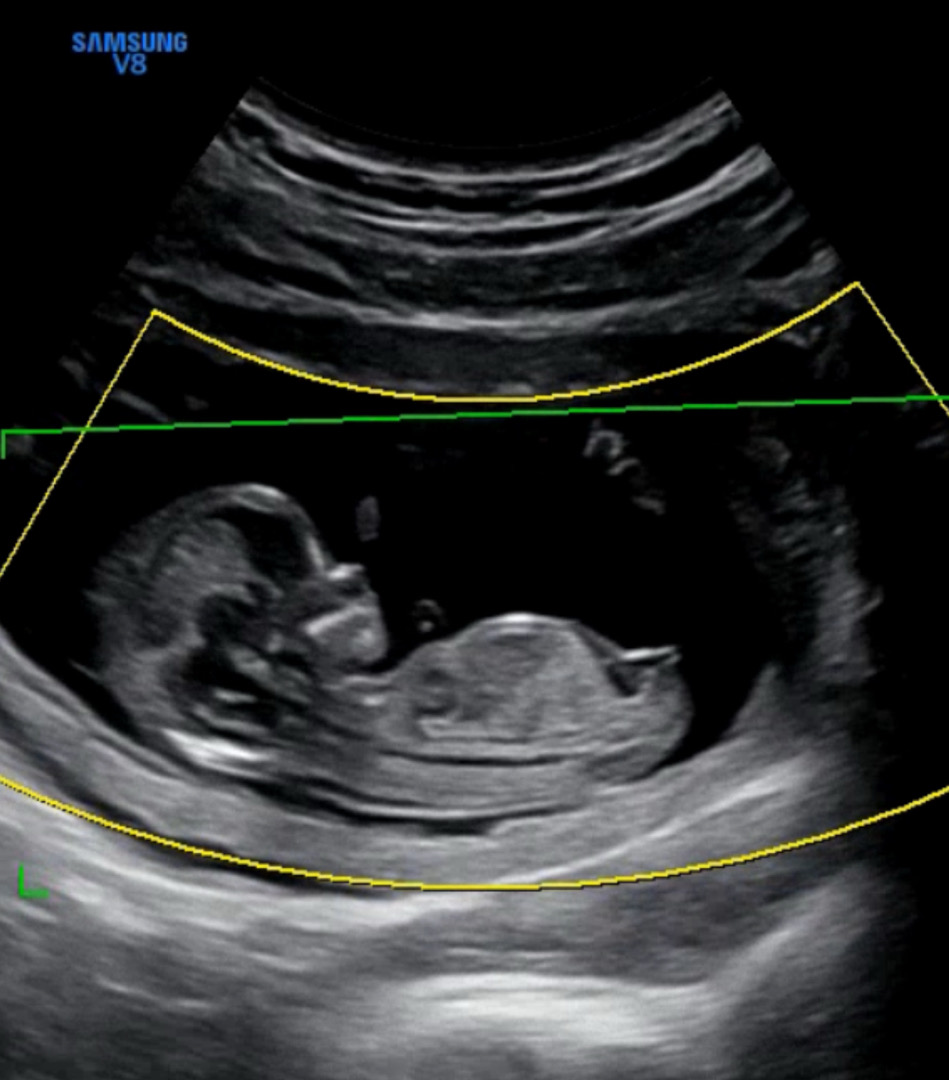

각도법 봐주세요! 12주 4일차

각도법 고수님들 한번 확인해주세요ㅎㅎ

딸 각도 같아요

저는 딸 같아 보여용!